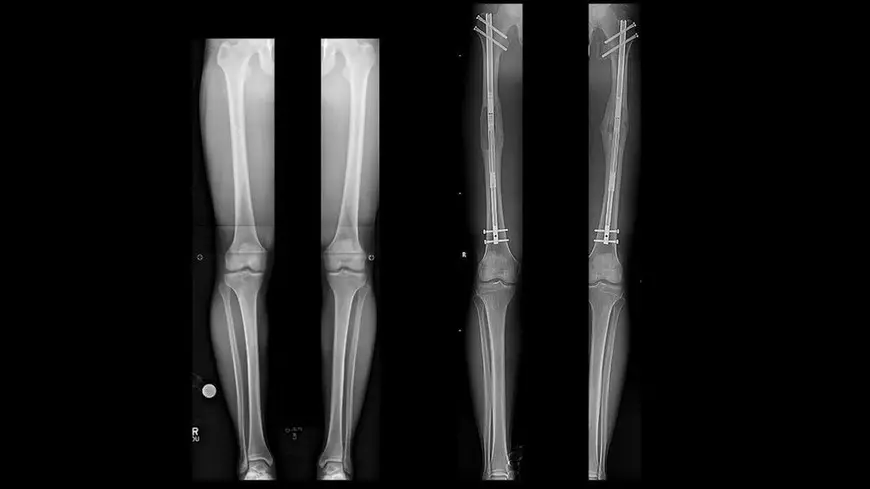

Mai întâi, se forează o gaură în oasele picioarelor, care sunt apoi sparte în două. O tijă metalică este montată chirurgical în interior și menținută în poziție de mai multe șuruburi. Tija este apoi prelungită încet cu până la 1 mm în fiecare zi, extinzându-se până când pacientul atinge înălțimea dorită și oasele lor se pot vindeca.

Pacientul necesită apoi câteva luni de reabilitare zilnică pentru a construi mobilitatea. Procesul este plin de riscuri de complicații, de la leziuni nervoase și cheaguri de sânge până la posibilitatea ca oasele să nu se sudeze.